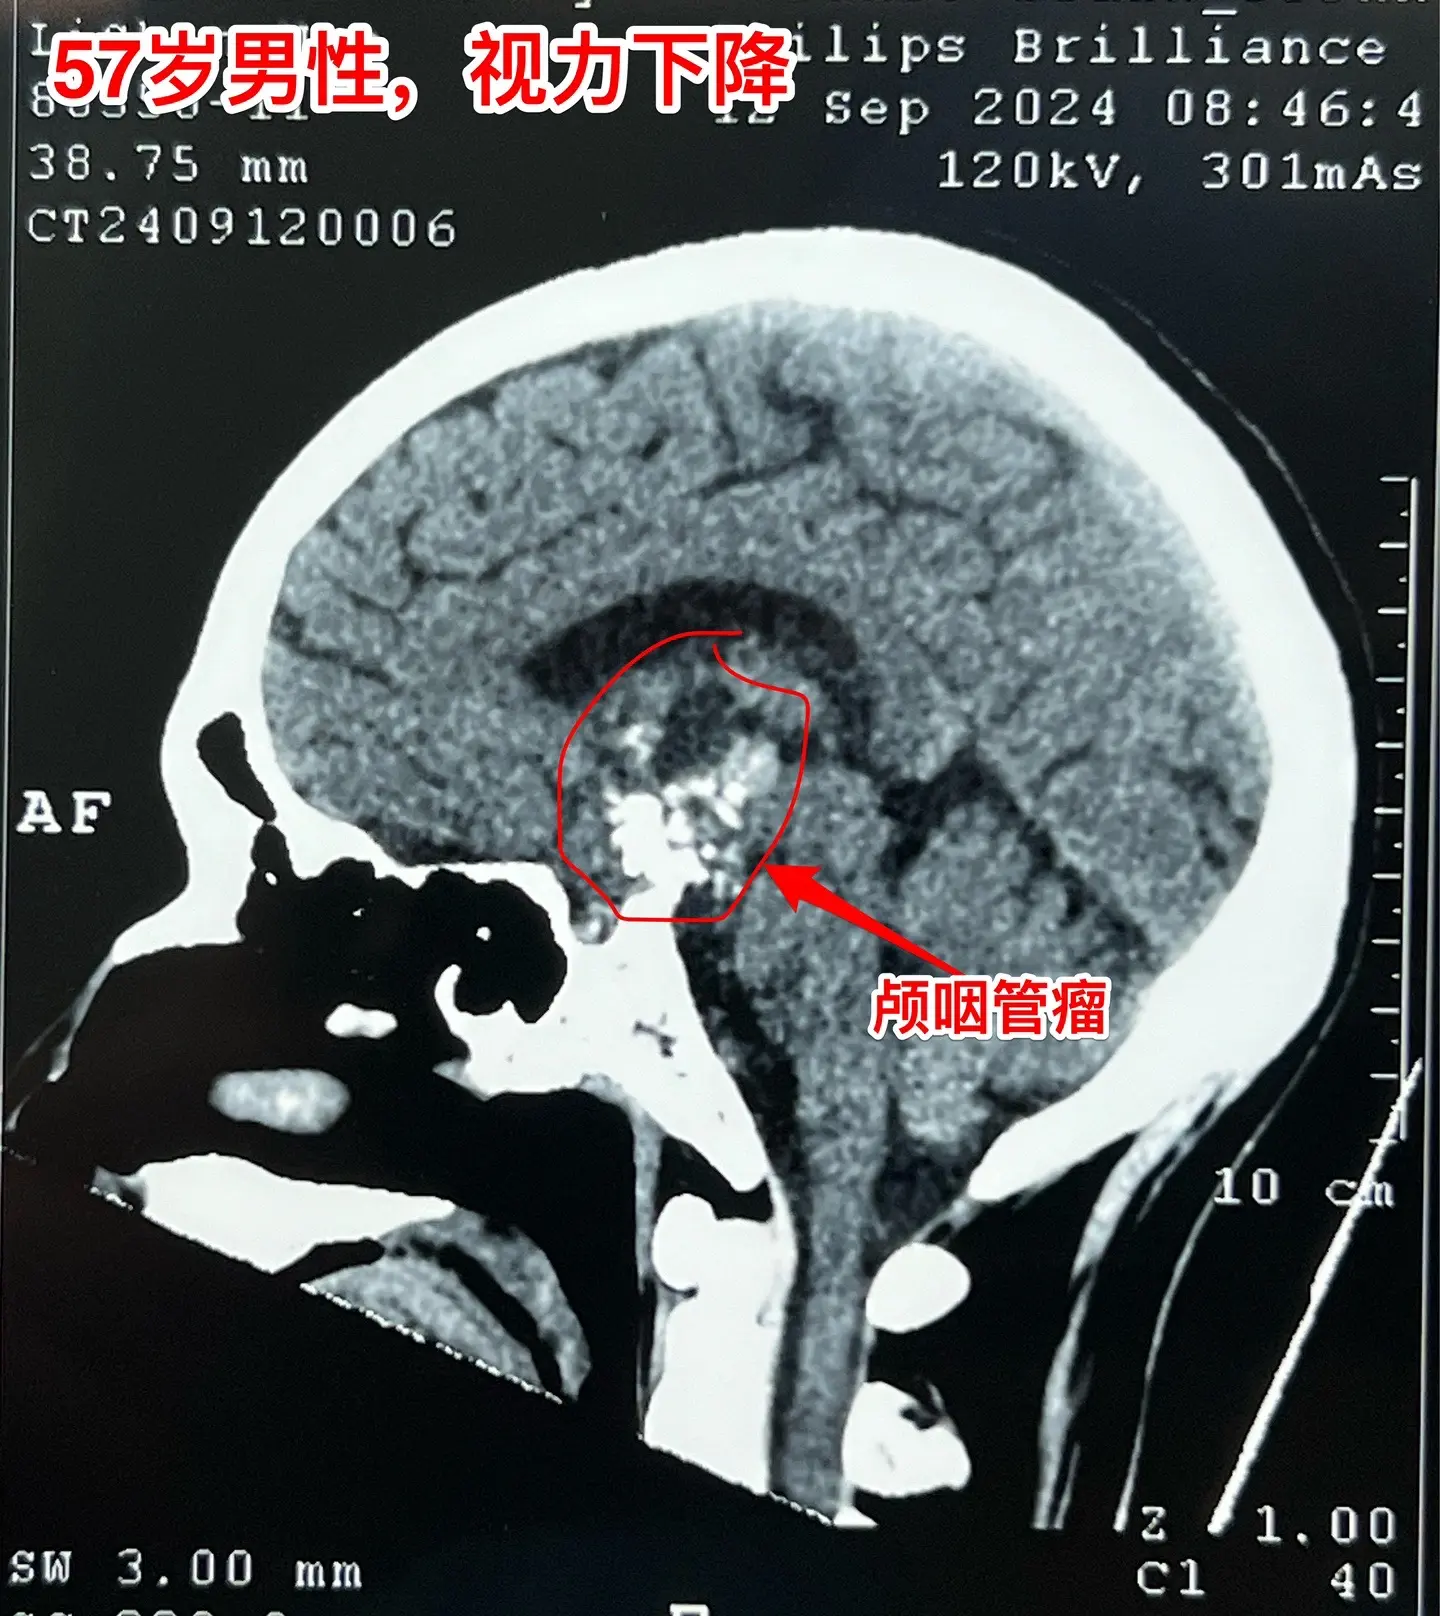

57岁男性,颅咽管瘤导致视力下降。病人因视力下降、消瘦到外院检查发现颅咽管瘤。如图所示,肿瘤体积比较大,有大量的钙化斑,是典型的造釉性颅咽管瘤。2024.9.20在我院行开颅手术,将颅咽管瘤完全切除。手术后患者视力明显改善了。十一前已经出院了,出院前体重有增长。